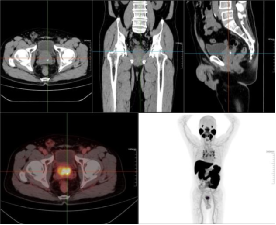

老年男性,前列腺增生病史,发现左侧颈部肿块多年,排尿困难,分叉5年,血精,怀疑前列腺肿瘤。PET/CT图如下。第一排为CT图,第二排分别为融合图、MIP图。

前列腺体积增大,并向前上凸入膀胱,腺体密度欠均匀,最大横径约55.3mm,前后径约42.5mm,腺体内点、条状高密度影,放射性摄取局限性增高,腺体中央部和外周部为著,摄取增高范围约38.1mmX27.3mm,SUVmax7.09,前列腺包膜局部略毛糙,考虑前列腺Ca,肿瘤突破包膜不除外。

经PSMA PET/CT显像检查准确发现了隐匿的转移灶,临床医生及时调整穿刺位点及治疗策略。